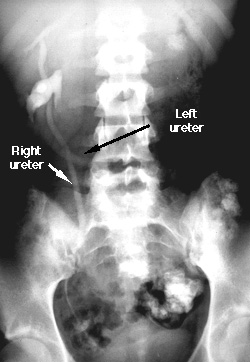

Crossed Fused Ectopia of Kidney